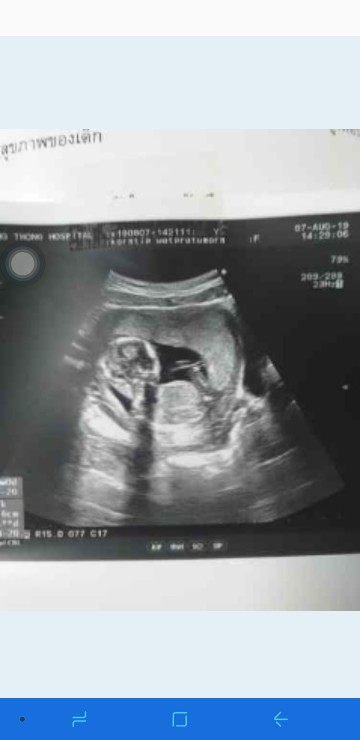

ตอน 12 week ค่ะ

13 week จ้า